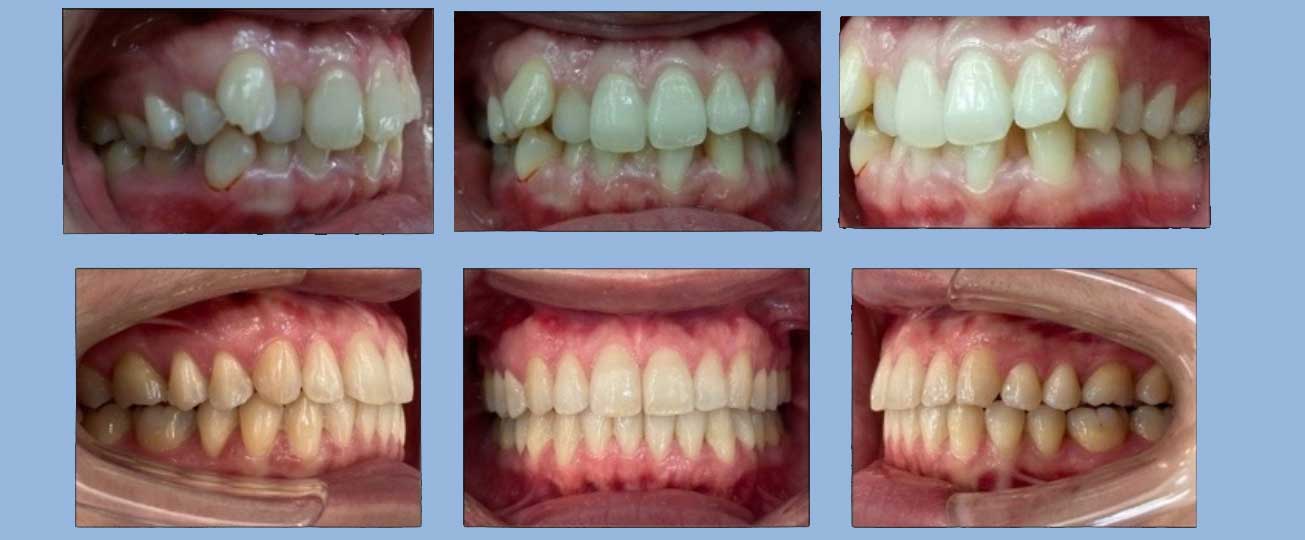

湯先生 (21歲) 矯正完成

狀態 : 牙齒暴和擁擠、沒拔牙